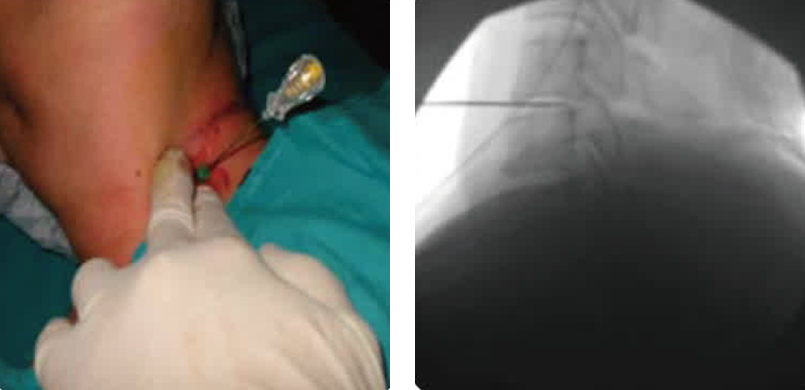

C-arm 유도하 신경차단술

대학병원급 최신식 C-arm을 이용해 척추 통증 부위를

실시간 투시하면서신경 주변에 치료 약물을 직접 주입.